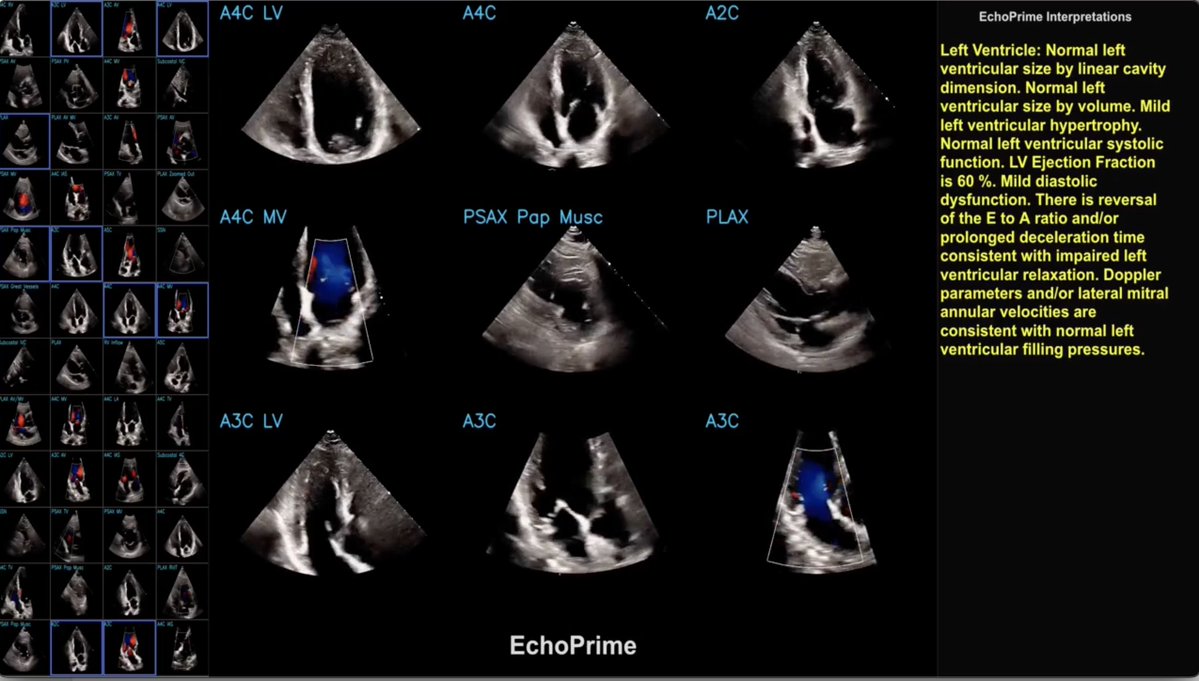

A big advance in the comprehensive A.I. interpretation of echocardiographic images today @Nature https://t.co/cV8sh7nZF3 @David_Ouyang @milos_ai @CedarsSinai and collaborators